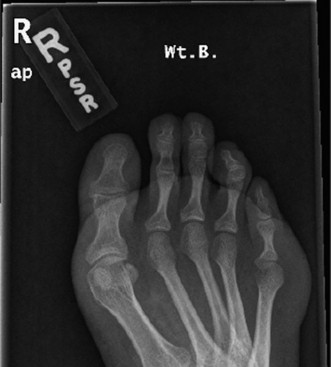

A 16-year-old male presents noting frequent sprains to his right ankle. He notes that he rolls his right ankle several times a day, and also describes pain along the lateral border of his foot. His left ankle is similarly symptomatic, but not quite as severe. Radiographs are obtained (Figs. 5–3 and 5–4).

Figure 5–4 AP weight-bearing radiograph of the foot.